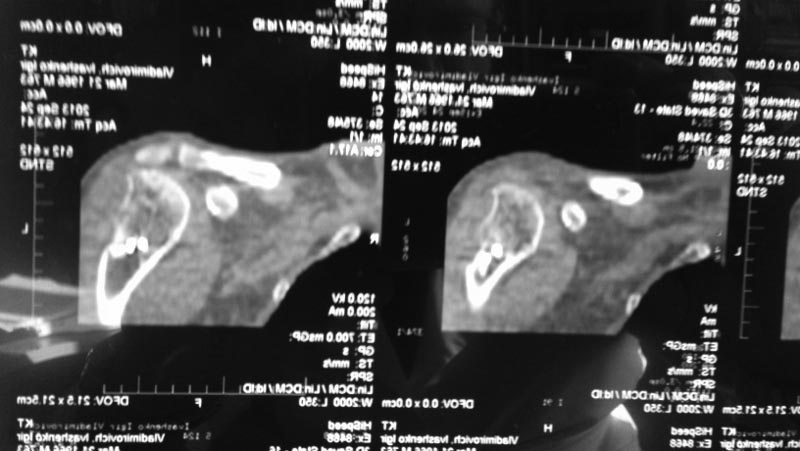

[Ortho] Застарелое повреждение ВМП, дефект головки плеча

Дополнительные снимки

Имя     : IMG_20140403_100642 (800x451).jpg